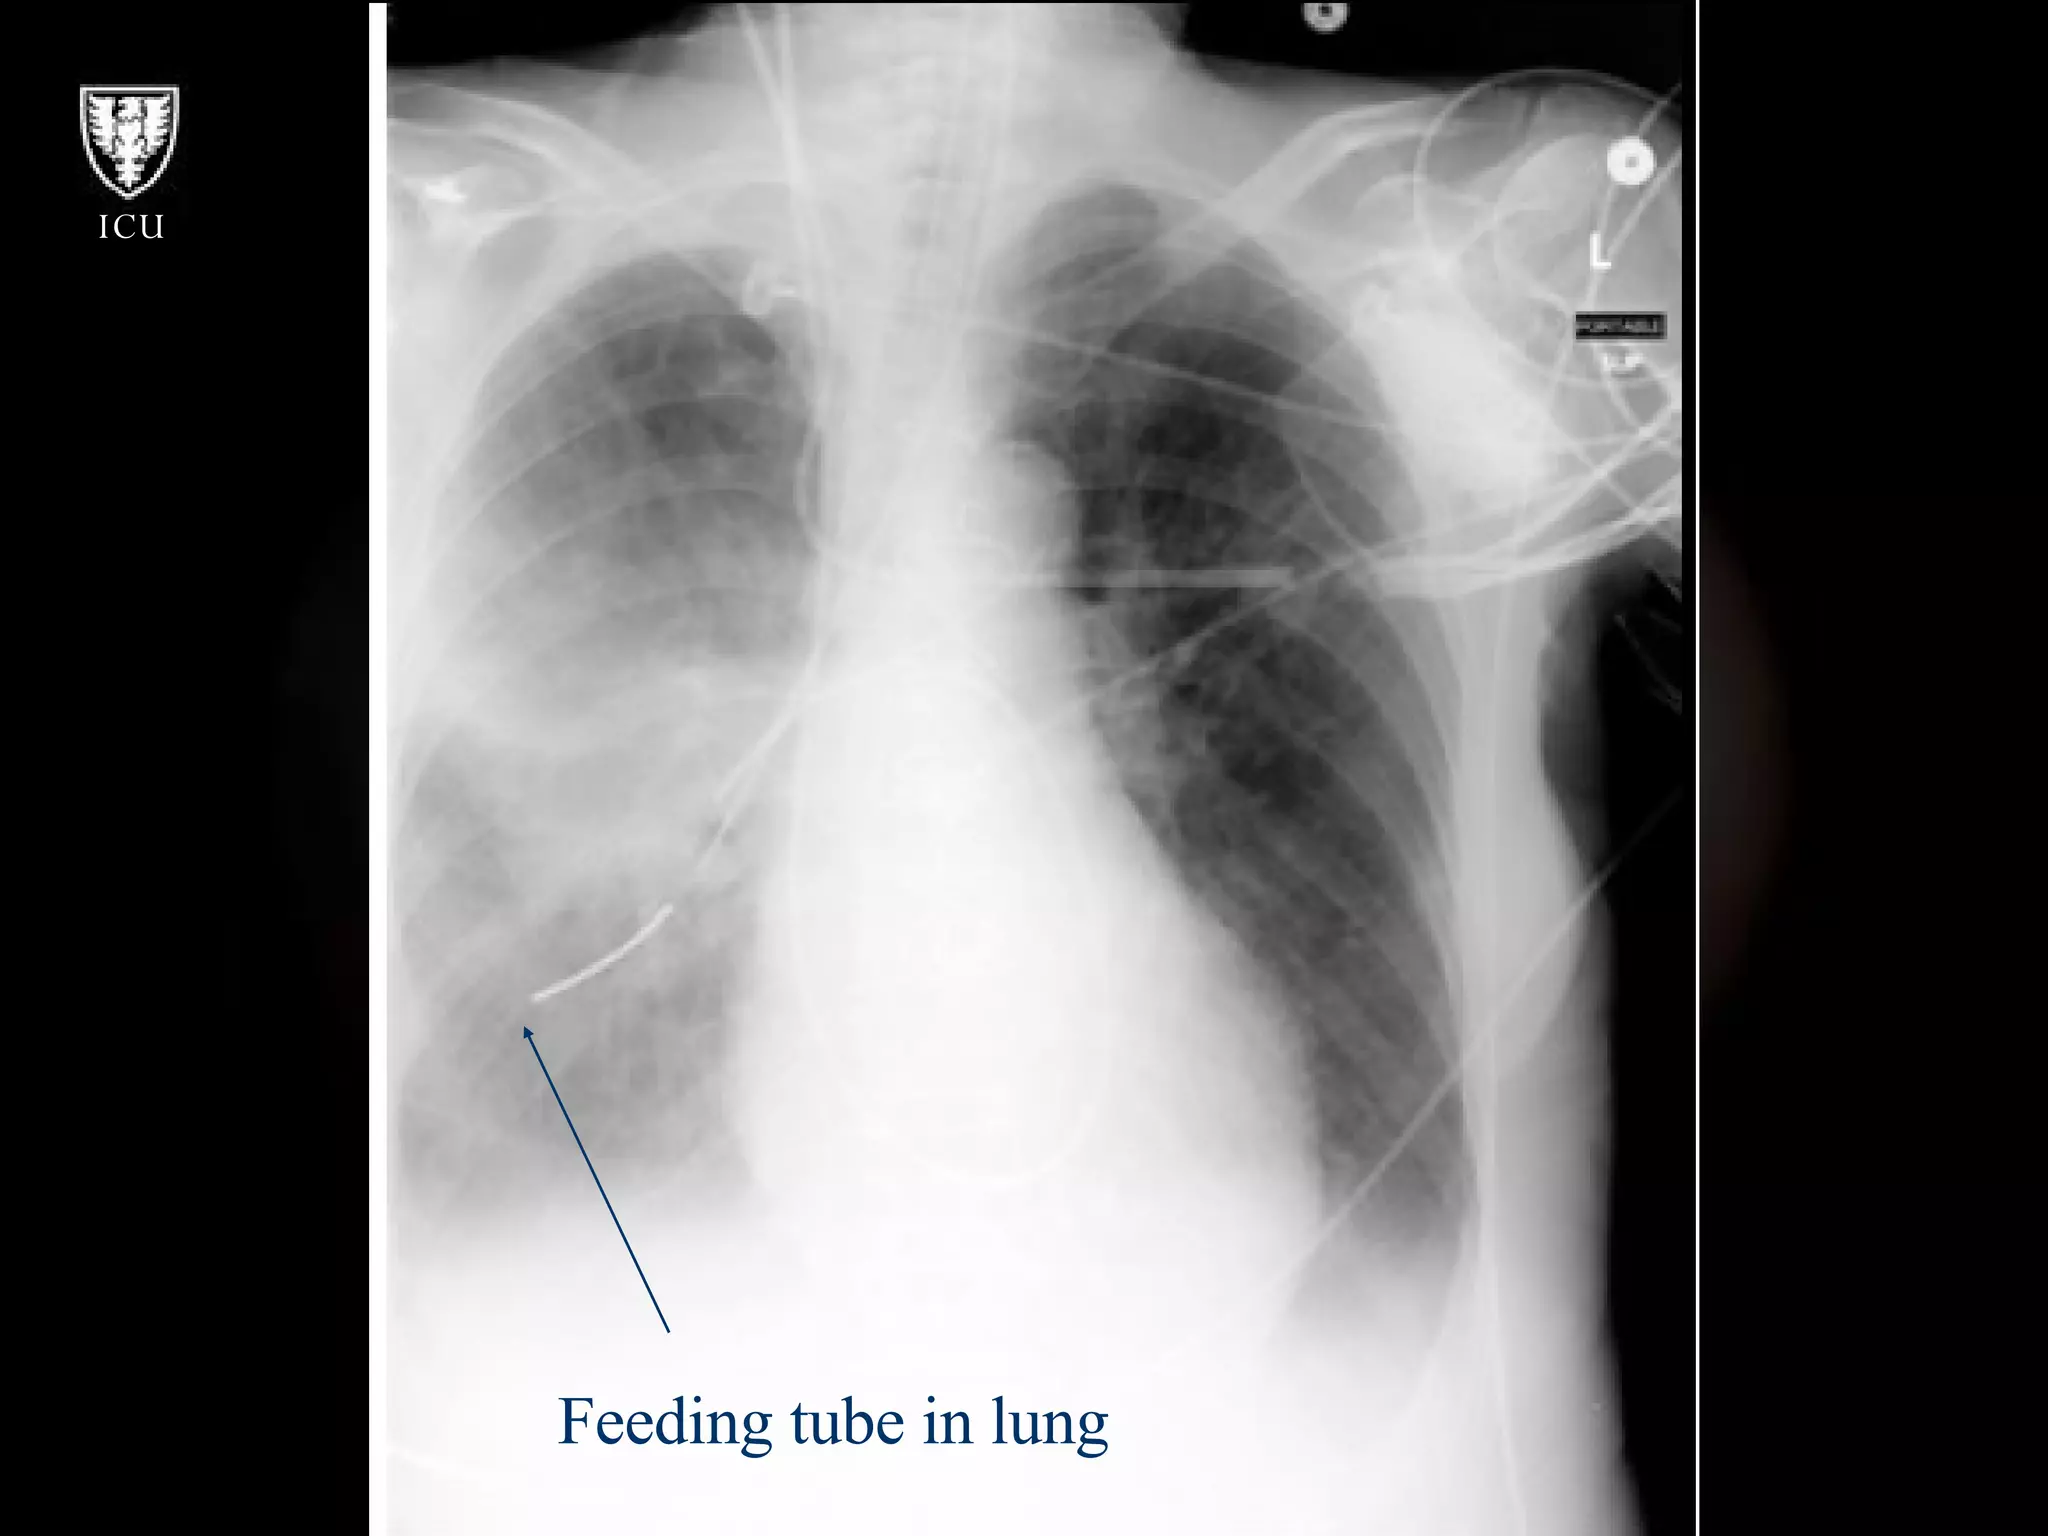

What’s Wrong With These Pictures?

Feeding tube in lung

Feeding  Tube in  RLL

What’s Wrong WithThese Pictures?